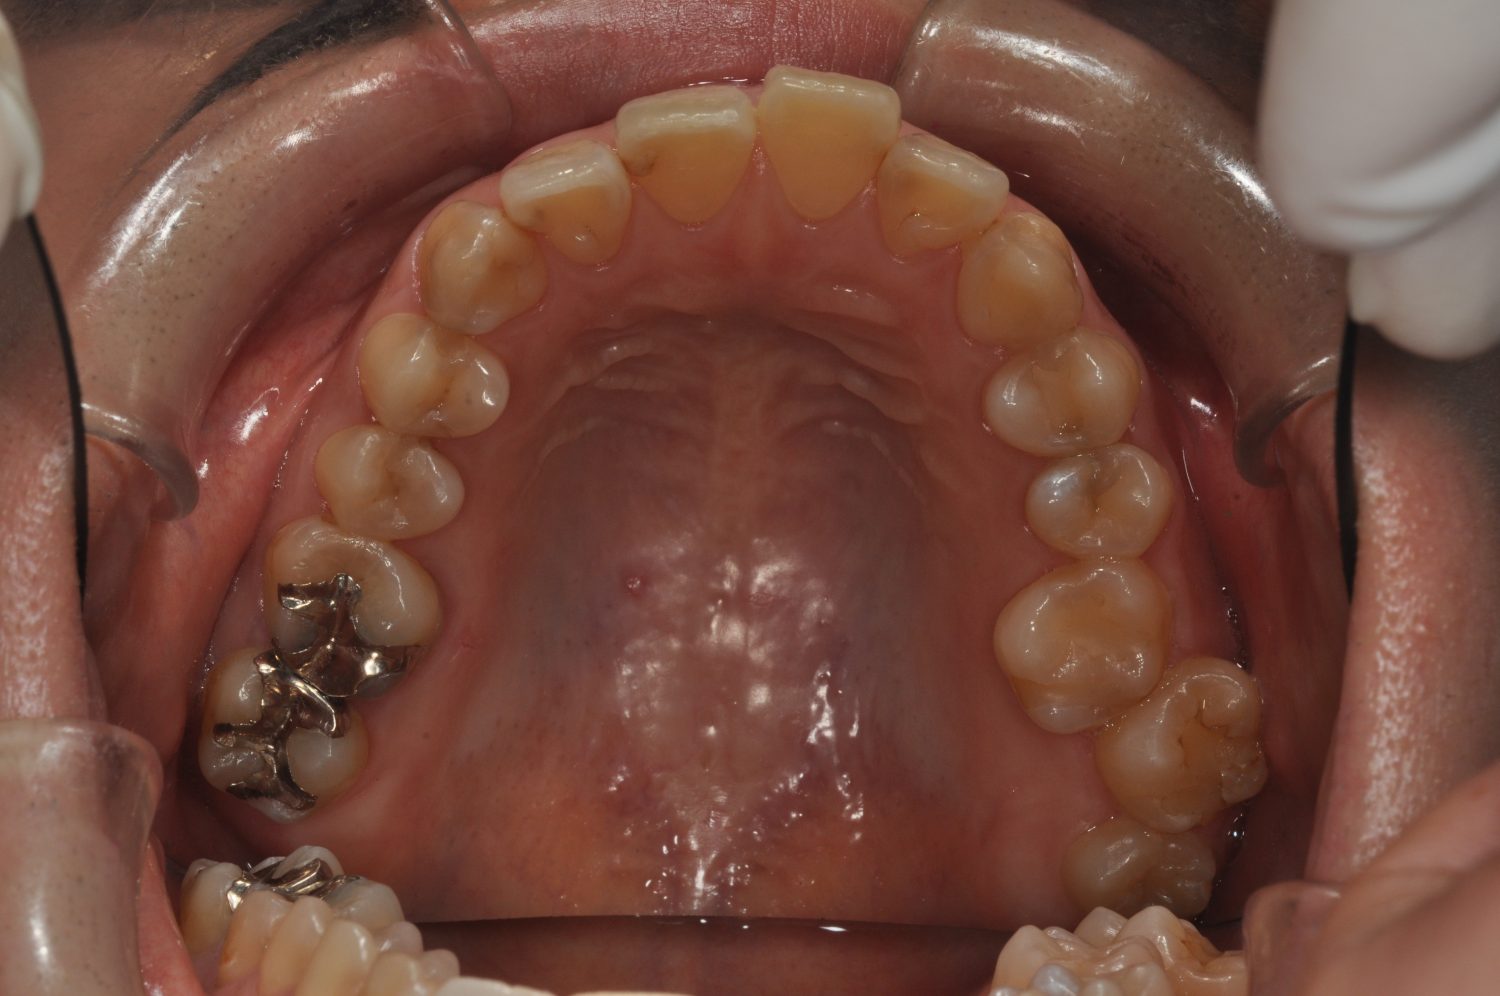

| 主訴 | 前歯の出っ歯を直したい |

| 治療内容 | 上下顎とも標準範囲であるが、上下顎前歯ともに唇側傾斜による、上下顎前突。上顎小臼歯を抜去し配列を行うこととした。 |

上下顎前歯の唇側傾斜による上下顎前突。オーバージェットが大きいため、上顎のみの抜歯で配列を行った。